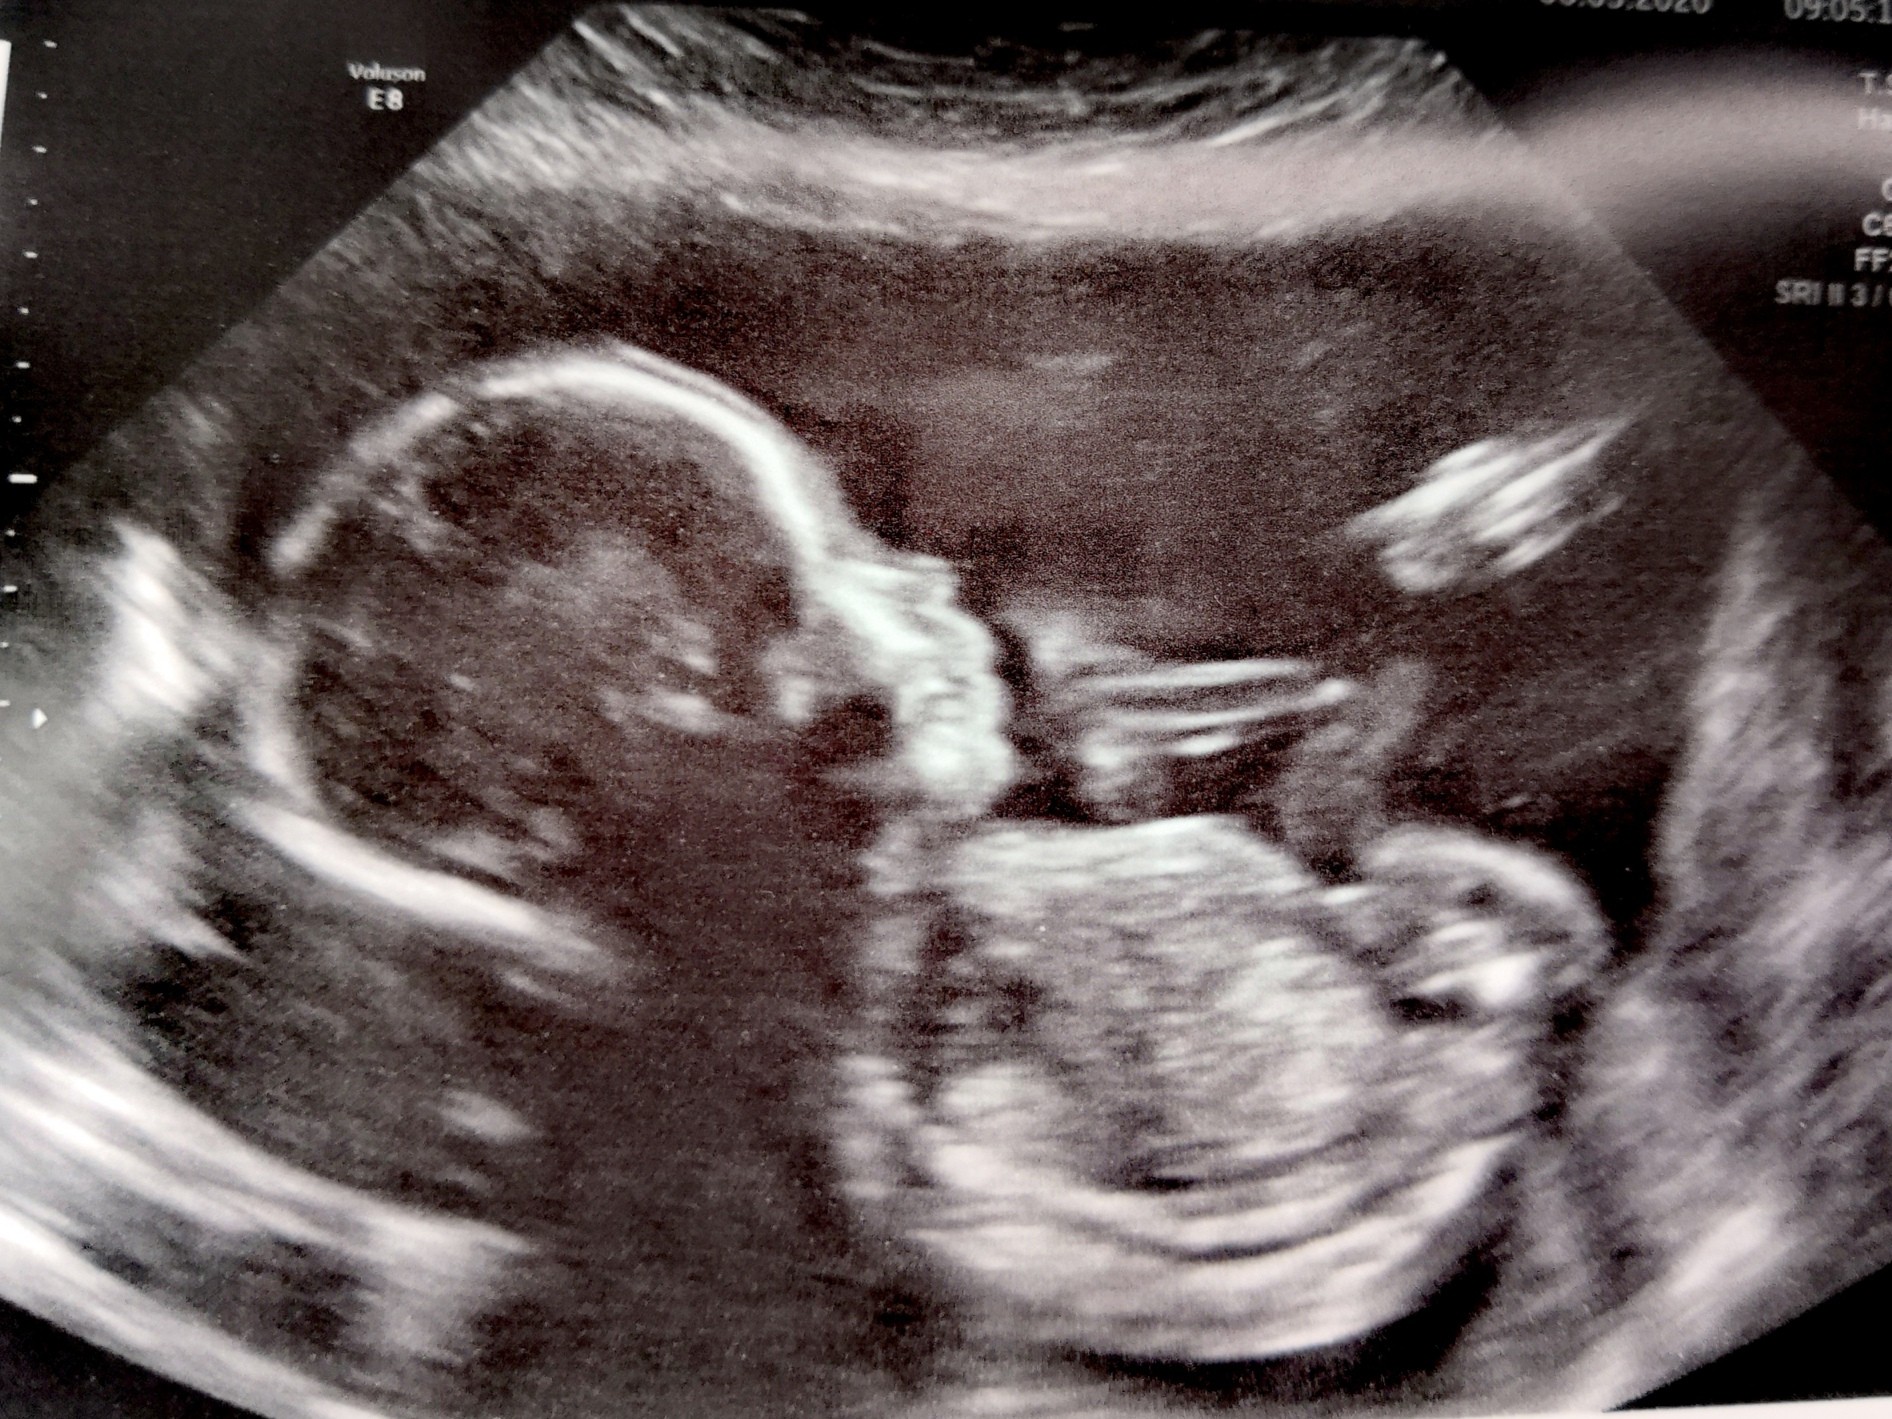

Moja malutka dzis, 20 tyg 🥰 tak już Ją kocham musi być dobrze.. To czekanie mnie dobija..

IMG_20200506_091545.jpg

Moja malutka dzis, 20 tyg [emoji3059] tak już Ją kocham musi być dobrze.. To czekanie mnie dobija..

Zobacz załącznik 1115951